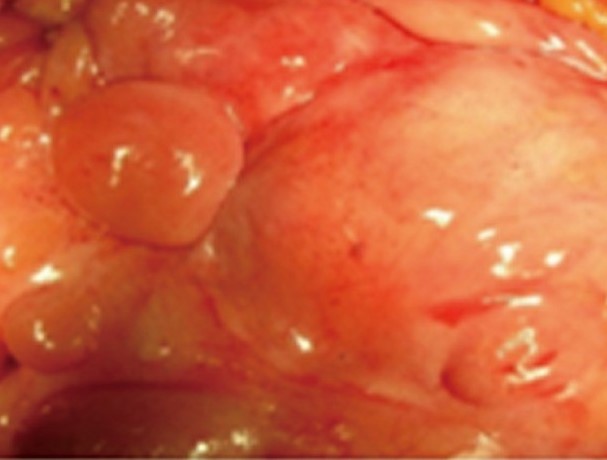

Resected obstructed ileal loop. Blue circles enclose the metastatic foci (Courtesy Dr. V. Penopoulos)

After opening the specimen, the metastatic foci are clearly visible (Courtesy Dr. V. Penopoulos)